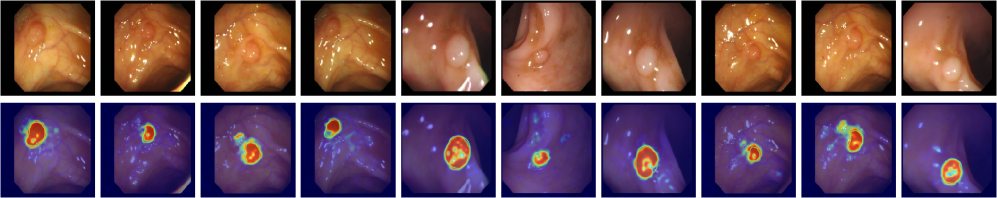

Here, we assess how well the features learned on industrial datasets generalize to domains far from the industrial domain. To this end, we evaluate Crane on seven medical datasets spanning diverse applications, including skin cancer detection in photography images, colon polyp identification in endoscopy images, thyroid nodule detection in ultrasound images, and brain tumor detection in MRI images. The goal is to determine whether the model has developed a broader understanding of normality and abnormality.

Table 1 presents the results, showing a consistent image-level trend: both versions outperform prior SOTA by a similar margin, improving average performance by 2.2% to 3.6% across reported metrics. At the pixel level in medical datasets, Crane outperforms existing models and remains competitive with AnomalyCLIP, while Crane+ further improves AUPRO by 5.0% and F1-max by 2.3% over the SOTA, demonstrating strong zero-shot generalization across challenging medical benchmarks.

Appendix D Visual Analysis

To provide an intuitive comparison, we present anomaly maps generated by the top competing models: VAND, AdaCLIP, AnomalyCLIP and both versions of our model, Crane and Crane+, across industrial images from MVTec-AD, VisA, MPDD, BTAD, DAGM, and DTD-Synthetic, as well as medical images from ISIC, CVC-ClinicDB, and BrainMRI. The training settings are detailed in the ’Experiment Settings’ section (5). Note that BrainMRI only has image-level labels, and the provided sample is annotated by a medical professional. As shown in the Figure 3, VAND suffers from high false positive rates (FPR), while AdaCLIP exhibits a high false negative rate (FNR). AnomalyCLIP improves sensitivity by reducing FNR but still struggles with high FPR. By leveraging stronger semantic correlations among patches, Crane reduces both FPR and FNR over previous methods, yielding tidyier and more precise results. This effect is further enhanced in Crane+, demonstrating superior localization performance.